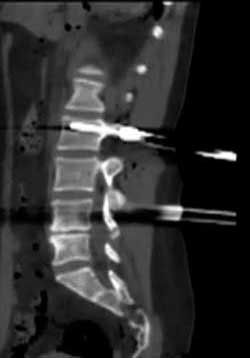

Jcm Free Full Text Thoracic Lumbar And Sacral Pedicle Screw Placement Using Stryker Ziehm Virtual Screw Technology And Navigated Stryker Cordless Driver 3 Technical Note Html